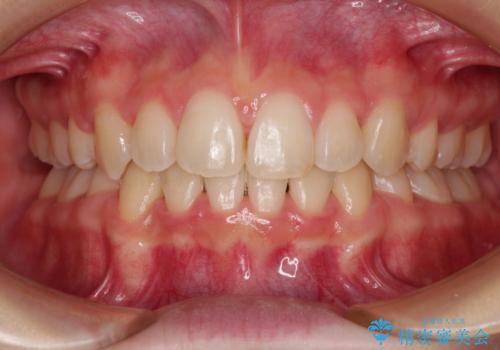

- 前歯の捻れを気にして来院された患者様です。

上顎前歯が捻れて前方に飛び出しており、下顎前歯もそれに沿うようにデコボコとなっていました。

IPR(歯と歯の間を削る処置)によりスペースを獲得して上下前歯のデコボコを改善し、インビザラインにて矯正治療を行うこととしました。

捻れていた前歯の形態が、先端が欠けていたり、一部むし歯処置により左右非対称の形態となっていたため、なかなかゴールが定まらず、治療期間がかかってしまいました。